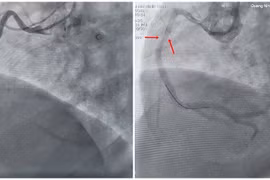

Dò động mạch vành là một tình trạng bất thường trong hệ thống mạch máu tim khiến lượng máu cung cấp cho cơ tim bị giảm, gây ra những triệu chứng như khó thở, đau tức ngực.

Trong lúc đưa con đi khám tại Bệnh viện Nhi đồng Cần Thơ, người phụ nữ 26 tuổi cảm thấy mệt và nhập viện trong tình trạng nguy kịch, khó thở, loạn nhịp thất có biến chứng ngưng tim 10 phút...